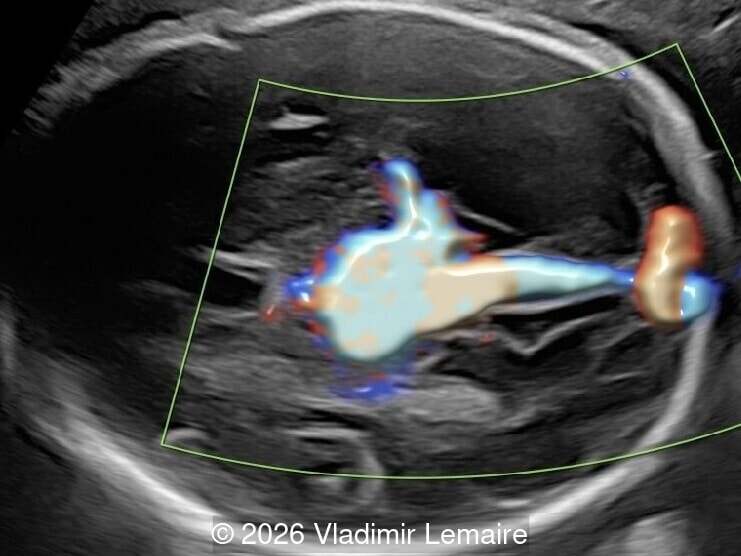

Intracranial arteries and veins in 3D color Doppler in combination with silhouette mode.

Image 4 Intracranial arteries and veins in 3D color Doppler in combination with silhouette mode.